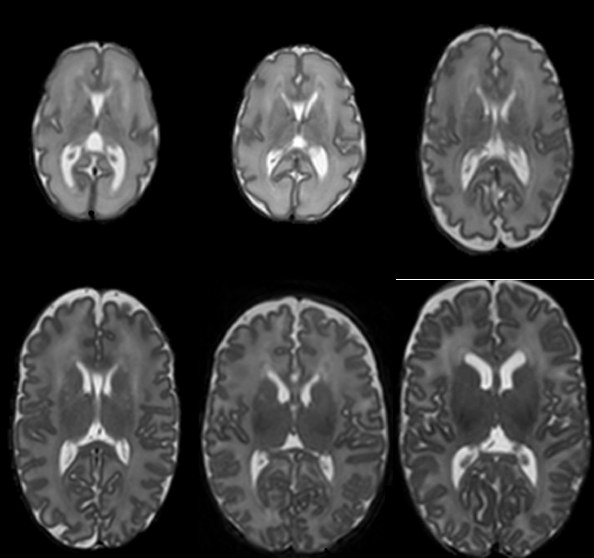

Refer to caption

(a) Fed-Camelyon16

(b) Fed-LIDC-IDRI

(c) Fed-IXI

(d) Fed-KITS2019

(e) Fed-TCGA-BRCA

(f) Fed-ISIC2019

(g) Fed-Heart-Disease

Figure 1: Heterogeneity of FLamby datasets. Best seen in color. 1(a): Color histograms per client. 1(b), 1(c) and 1(d): Voxel intensity distribution per client. 1(e): Kaplan-Meier survival curves per client. 1(f): UMAP of deep network features of the raw images, colored by client. 1(g): Per-client histograms of several features. Differences between client distributions are sometimes obvious and sometimes subtle. Some clients are close in the feature space, some are not and different types of heterogeneity are observed with different data modalities.

We qualitatively illustrate the heterogeneity of the datasets of FLamby. For each dataset, we compute a relevant statistical distribution for each client, which differs due to the differences in tasks and modalities of the datasets. We comment the results displayed in Figure 1 in the following. Appendix M provides a more quantitative exploration of this heterogeneity.

For the Fed-Camelyon16 dataset, we display the color histograms (RGB values) of the raw tissue patches in each client. We see that the RGB distributions of both clients strongly differ. For both Fed-LIDC-IDRI and Fed-KITS2019 datasets, we display histograms of voxel intensities. In both cases, we do not note significant differences between clients. For the Fed-IXI dataset, we display the histograms of raw T1-MRI images, showing visible differences between clients. For Fed-TCGA-BRCA, we display Kaplan-Meier estimations of the survival curves [kaplan1958nonparametric] in each client. As detailed in Appendix F, pairwise log-rank tests demonstrate significant differences between some clients, but not all. For the Fed-ISIC2019, we use a 2-dimensional UMAP [mcinnes2018umap] plot of the features extracted from an Imagenet-pretrained Efficientnetv1 on the raw images. We see that some clients are isolated in distinct clusters, while others overlap, highlighting the heterogeneity of this dataset. Last, for the Fed-Heart-Disease dataset, we display histograms for a subset of features (age, resting blood pressure and maximum heart rate), showing that feature distributions vary between clients.